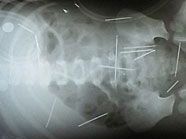

In Brasilien hat der Stiefvater eines Zweijährigen gestanden, 50 Metallnadeln in den Körper des Kleinkindes gestochen zu haben. Der kurz zuvor Festgenommene gab zu, dass er sich mit der Tat an seiner Frau rächen wollte, wie der zuständige Ermittler am Mittwoch (Ortszeit) mitteilte.

Die Röntgenbilder mit Nadeln

Der Mann sei von seiner Geliebten zu der grausamen Tat angetrieben worden, die ihm geraten habe, seinen Stiefsohn durch das Ritual zu töten, sagte der Polizist der Nachrichtenagentur AFP. Das Kind war am Sonntag mit Erbrechen und Schmerzen ins Krankenhaus gebracht worden, wo die entsetzten Ärzte beim Röntgen die Nadeln entdeckten. Der Bub lag am Mittwoch weiter auf der Intensivstation. Jetzt prüften die Ärzte seinen Zustand, um möglicherweise die Nadeln herauszuoperieren, die am dichtesten an lebenswichtigen Organen säßen: “Aber das könnte noch gefährlicher sein, als sie einfach steckenzulassen”, sagte eine Sprecherin.